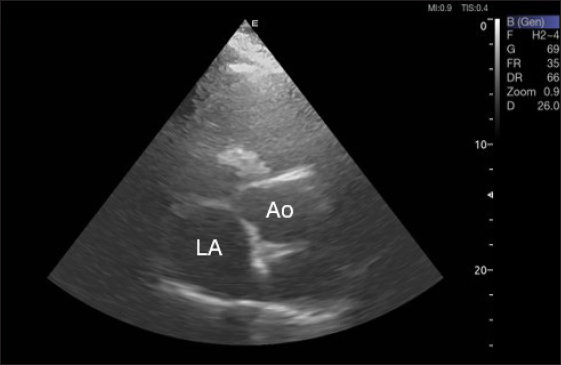

Fig. 3. Right parasternal short-axis view of 16 she-camel at great vessel level showing Ao=aorta and LA=left atrium.

Fig. 4. LA/Ao ratios for the right parasternal short axis of 18 racing camels at the great vessel level. Through the anatomical M mode.